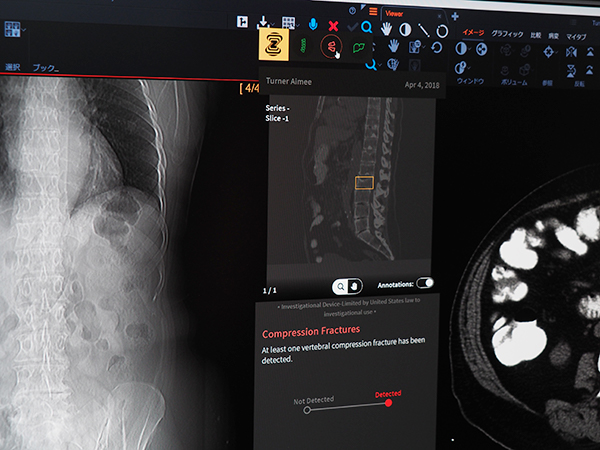

展示では,“Clinical Collaboration Platform”として医用画像情報システム「Vue PACS」や放射線情報システム「CARESTREAM RIS-J」の新機能を中心に紹介した。今年のITEMのトピックスともいえるAIへの取り組みとしては,RSNA2018でも紹介されたゼブラ・メディカル・ビジョン(ゼブラ社)のAIエンジンのVuePACSへの統合,自社開発の病変管理機能(リージョンマネジメント)やCTのspine自動ラベリングなどを紹介した(すべてW.I.P.)。画像データをサーバに登録した段階でAIによるスクリーニング終了しており,ワークリストオーケストレーターのワークリスト上には優先順位などをつけて表示される。

ゼブラ社のAIエンジンをVuePACSに統合